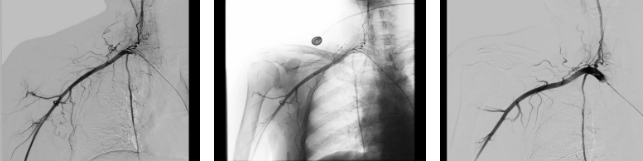

于黎明主任团队反复研究宋女士的病情,结合介入血管科的专业优势,大胆提出了“肩关节动脉栓塞术”的治疗方案。

当医生把这个方案告知宋女士时,她既惊讶又犹豫:“介入手术还能治肩痛?我之前从来没听说过。”医生耐心地为她解释:“你的肩痛与肩关节周围异常血管增生、炎症刺激有关,通过介入技术精准找到异常增生血管并进行栓塞,就能从根源上缓解疼痛,改善关节活动功能。”

入院三天后,于黎明主任团队为宋女士顺利实施了肩关节动脉栓塞术。整个手术创伤小、恢复快,全程没有明显不适。